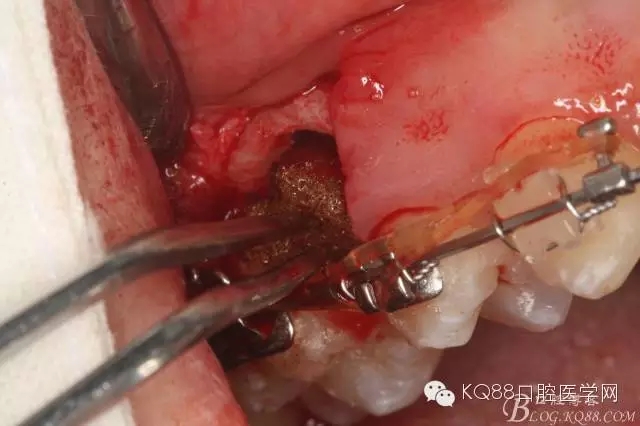

图15 .微创挺把15牙根纵分成近远中两块

图16.微创挺挺松近中根面部分,从16与14之间间隙出来

图17.血管钳取出近中部分15牙根

图18.取出近中部分后,接着挺松15牙根的远中部分